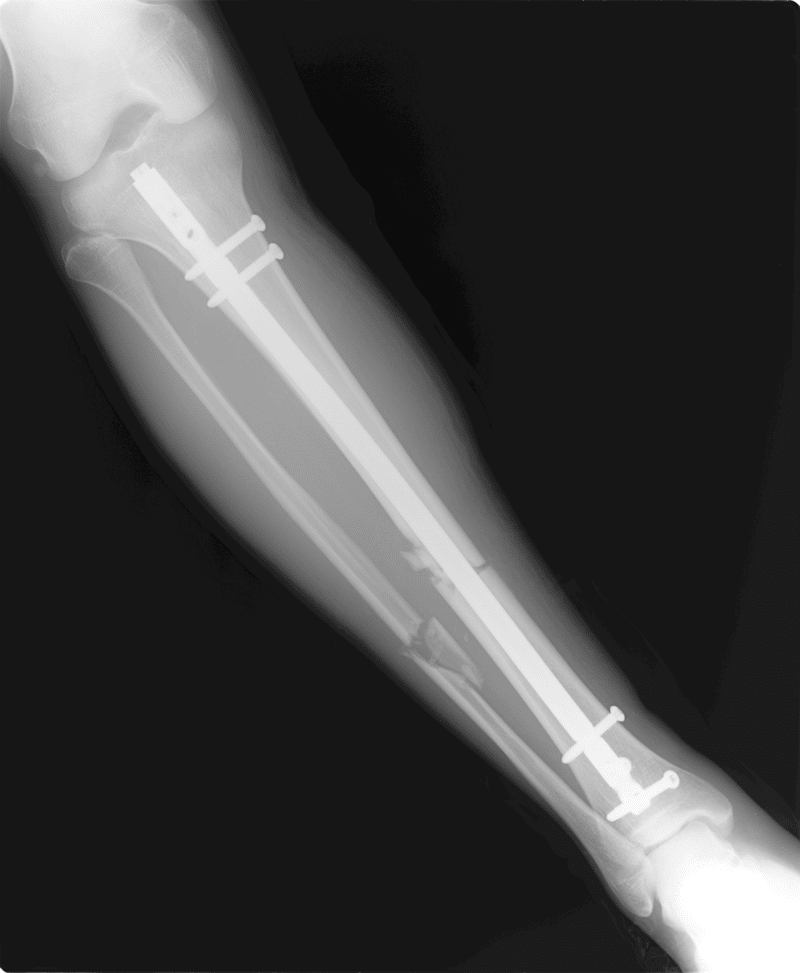

Oct 30, · 骨延長経験者のGen (@Gen_ilizarov)です。 18年に10cmの骨延長イリザロフ手術を受け、167cmから177cmに身長を伸ばしました。 東欧アルメニアに5ヶ月滞在し、帰国後3ヵ月で日常生活に復帰してます。 費用は全部で500万円でした。無形成症などの低身長に対して両あしを伸ばし、身長 を高くすることができます。 方法は、まず手術で骨を切り離し、人工的に骨折 伸ばすスピードは1日に05mm~1mmで、スピーNov 03, · 『背を伸ばす手術』から2年後の歩き&走り ~18年にイリザロフ手術で身長10cm伸ばしたその後~

Sep 12, 13 · そんなヴァニラが今度は、現在152cmである身長を伸ばすため、イリザロフ法という手術を行うのだとか。 身長を10cm伸ばす予定だった人はOct 04, · 脚の骨を切断、伸縮可能な装置を挿入 体の中では何が起きるのかというと、脚の骨を切ってそこへ伸縮する装置を挿入するのだ。 ただし、身長が伸びたことが一目で分かるまで1年近くかかる、という結果が出ている。 院長はこう説明する。 「大腿骨か脛骨(下腿骨)のいずれかを切って装置を挿入します。 この装置を調節し、ゆっくり骨を伸ばして身長をOct 09, · 週刊誌の裏表紙広告かと思ったらForbesの記事だった。 約800万円で身長が15cm伸びる手術が受けられるという内容( Forbes )。 ラスべガスにあるクリニックが立ち上げだ事業だそうで、腿骨か脛骨を切断し、そこに伸縮する装置を挿入する。 自分でリモコン操作し、毎日1mm伸びるようにすることで身長が伸びるとしている。 手術時間は1時間半ほどで、すでに約30人の

Oct 04, · 手術後には治療期間が続く。さらに、リモコン操作で1日1ミリずつ身長を伸ばすように管理するのは患者自身だ。 自分の骨の中に釘やボルトを仕込んだ「鉄人」になる心配はない。1年経てば、装置や固定具も外せるし、骨が生涯縮むことはないという。Ilizarov surgery made me 10 cm taller I stayed in Armenia for 5 months in 18 Femur 5cm tibia 5cm = 10cm, by LON (Lengthening over nails) method It cost 48,000 USD included all fee 3Jul 19, 19 · 脚延長手術で身長を伸ばすPart8176cm以上禁止 スネか太ももどちらか片方で10cm伸ばしたら重大な合併症が起きる パリハーならスネはLON、太ももはプリサイスまたはストライドでやれば、ぎりぎり700万円くらいに収まる可能性がある